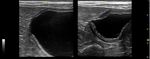

(a)                                                             (b)

Figure

Figure7.7. Two

Twolongitudinal

longitudinalultrasound

ultrasoundimages

imagesofofthe

theurinary

urinarybladder

bladderofofaadog

dogwith

withanan intramural

intramural

vesicourachal

vesicourachaldiverticulum.

diverticulum.TheTheimages

imagesshow

showtwo

twodifferent

differentvolumes

volumesofofurine

urineinto

intothe

thebladder

bladderlumen.

lumen.

(a)Overly

(a) Overly distended:

distended: the

thediverticulum

diverticulumappears

appearsasas

a not very

a not    visible

very      focalfocal

visible   depression  in thein

depression    cranial-ventral

the cranial-

aspect of

ventral     the bladder,

aspect   of the with  thinning

bladder,  withofthinning

the correspondent    bladder wall;bladder

of the correspondent        (b) ddequately

wall; (b) distended:

ddequatelythe

diverticulum

distended:   theappears   as an evident,

diverticulum   appears focal,

as an evagination   in the

evident, focal,     cranio-ventral

evagination    in theaspect  of the bladder.

cranio-ventral   aspect of

the bladder.